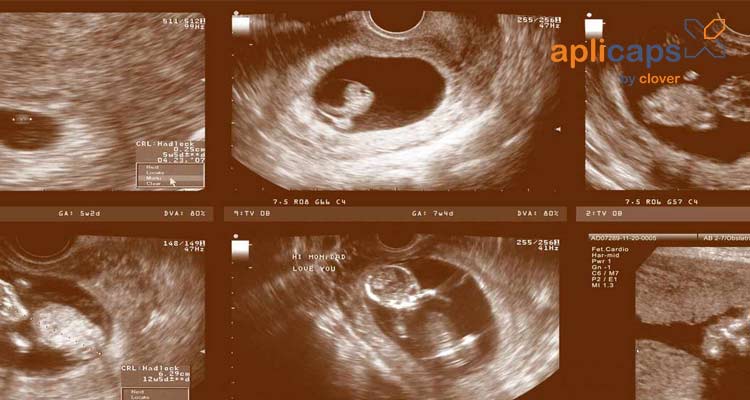

Siêu âm: Nhờ siêu âm thai sẽ giúp mẹ biết được chính xác quá trình phát triển của em bé trong suốt thai kỳ. Đây là cách bác sĩ tính được tuổi thai và ngày dự sinh đúng nhất so với những phương pháp khác. Thông qua những chỉ số về đường kính lưỡng đỉnh, kích thước thai nhi, chiều dài xương đùi.

Hình ảnh siêu âm thai nhi 20 tuần khoẻ mạnh

Khi siêu âm thai ở tuần 20 mẹ có thể biết rõ hơn về em bé của mình có đang phát triển khỏe mạnh không. Bác sĩ thông qua siêu âm sẽ kiểm tra được tất cả bộ phận của thai nhi và các chỉ số cần thiết.